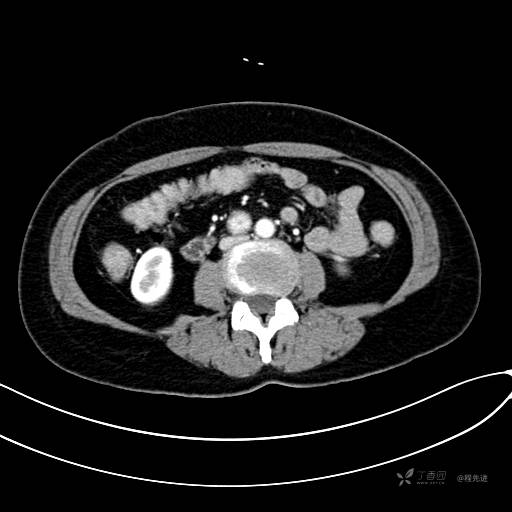

CT增强动脉期